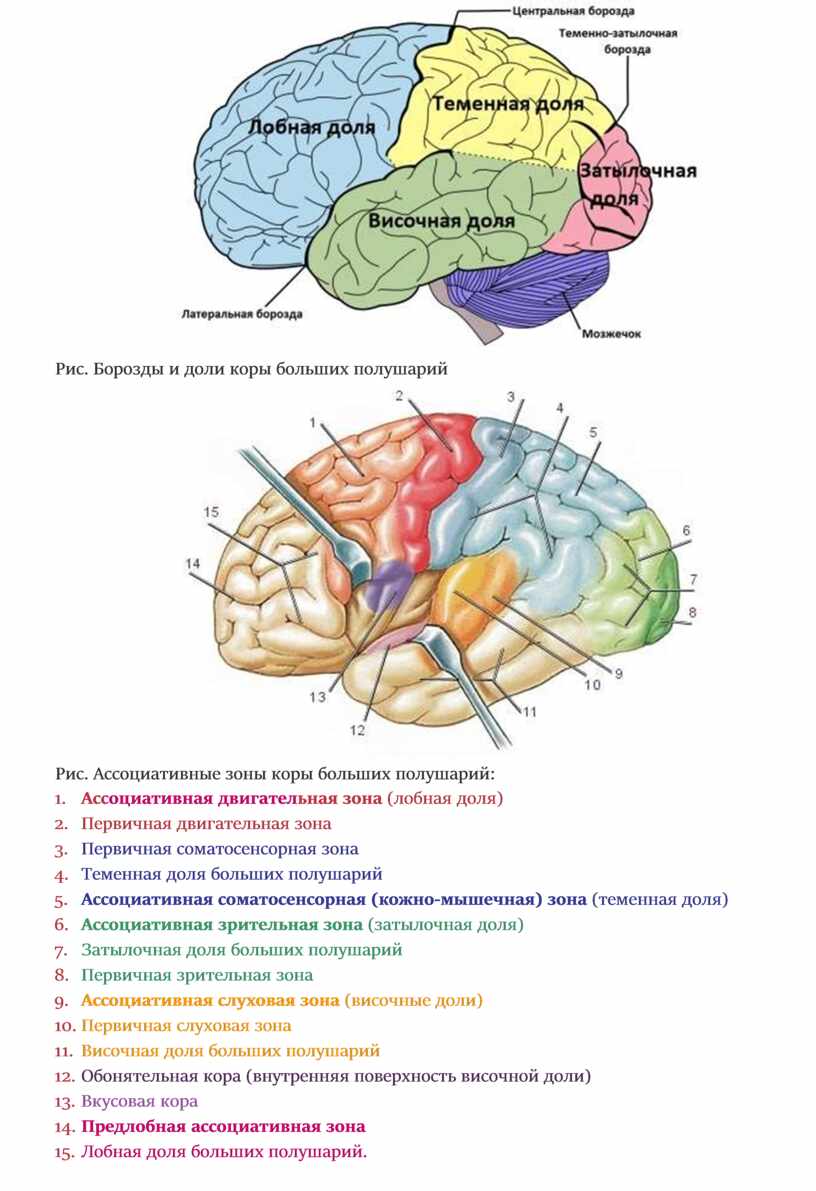

Схема чувствительных зон новой коры мозга